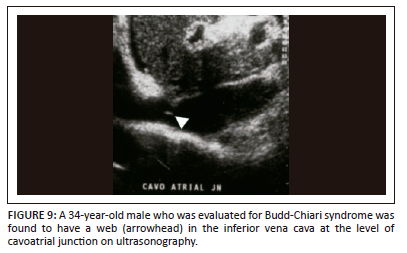

Inferior vena cava membranes and webs

These are uncommon IVC findings attributed to congenital vascular anomalies or the sequela of thrombus formation.9 North American and northern European populations are rarely affected. There is usually an underlying hypercoagulable state and they present acutely. Outcomes are usually fatal. Asian and South African populations are more commonly affected in whom it eventually leads to congestive cirrhosis.28 The onset is insidious in these patients.7,9 A complete or fenestrated membrane or a segment of fibrotic occlusion in the intrahepatic IVC with prominent intrahepatic and extrahepatic collaterals is seen on imaging (Figure 9). Inferior venacavography can be helpful in confirming the diagnosis. Endovascular treatment to relieve portal pressure can be performed depending on the severity of the associated liver disease.7,9,29 The association between membranous obstruction of the intrahepatic IVC, Budd-Chiari syndrome and HCC is well established.7